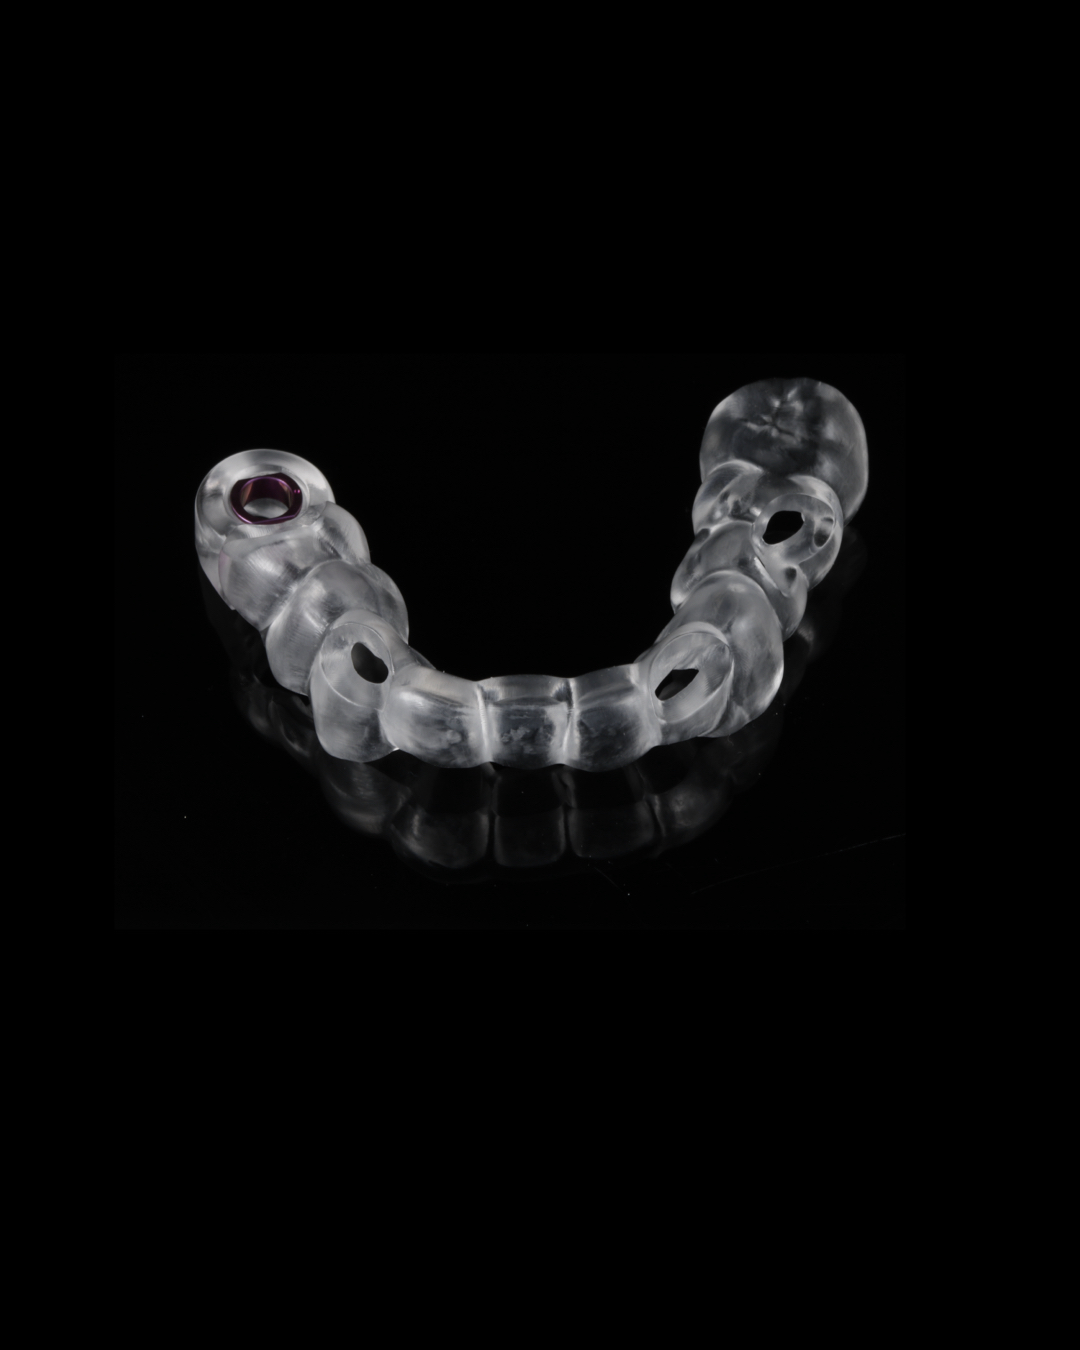

Durch die Vielzahl an Möglichkeiten, die diese Programme bieten, stellen wir vollnavigierte Bohr- und Pilotbohrschablonen sowie einfache OP-Schablonen her.